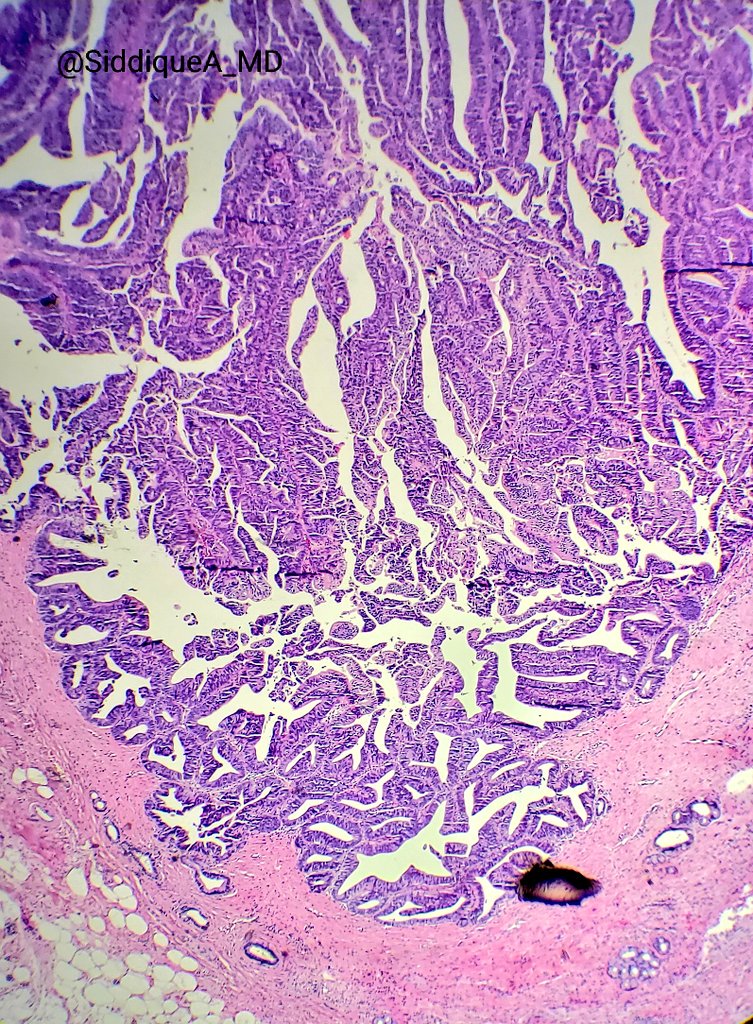

I'm obsessed with papillary lesions of the pancreatobiliary tract these days :D beautiful case of intraductal papillary neoplasm of cbd. No invasion.

#gipath#papillary#biliary pic.twitter.com/p2O4dNwp2J